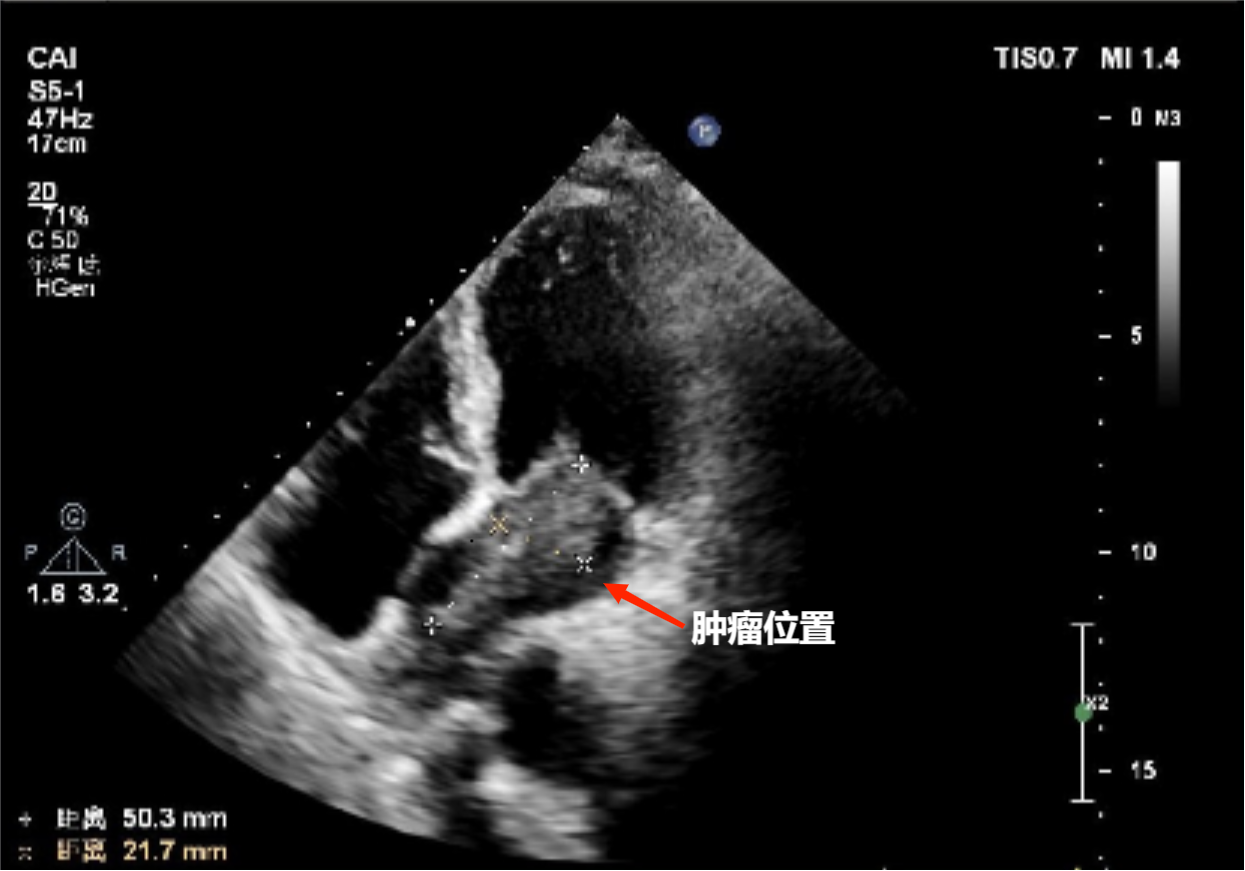

今年7月份,家住化州的洪爷爷突发气促,被家人送到茂名市人民医院治疗。入院后,呼吸与危重症医学科一区的主管医生李晓才接诊了洪爷爷并第一时间为洪爷爷进行了细致检查及病史询问,检查结果发现洪爷爷的左心房长了一个直径大约有5厘米的肿物。呼吸与危重症医学科一区遂邀请心血管外科陈景伟主任团队参加会诊、制定手术方案。

会诊过程中,陈景伟结合影像检查结果及多年丰富的临床经验,判断洪爷爷这颗心脏肿物为心脏粘液瘤可能性大。肿瘤碎屑脱落可能导致脑血管、心肌血管及下肢动脉等循环血管的栓塞,并且由于该肿物体积较大,已经坠入二尖瓣开口,如不尽快进行手术切除,一旦二尖瓣开口突然堵塞,洪爷爷将面临生命危险。但对洪爷爷这种已经有90岁的高龄、全身各器官功能已处于退化阶段,且患有慢性阻塞性肺病40余年的患者来说,要为他完成心脏外科手术,是一个严峻考验。